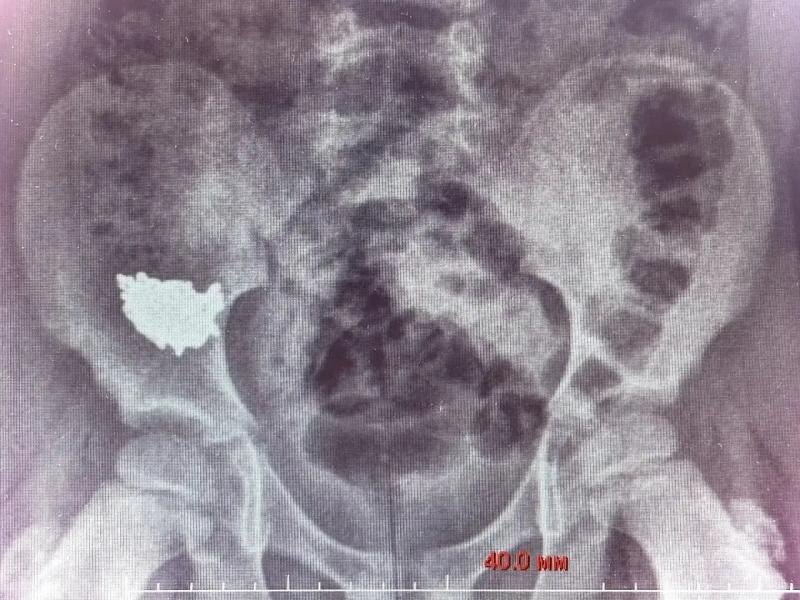

В Воронеже врачи ОДКБ №2 успешно удалили из брюшной полости ребёнка 20-сантиметровую цепочку. Он её случайно проглотил во время игры.

Как рассказали в региональном Минздраве, медики после сделанного рентгена увидели, что инородное тело находится в правой подвздошной области (часть тела человека, расположенная внизу живота). Пациента госпитализировали.

«Снимки на третьи и четвёртые сутки после обращения показали, что цепочка не двигается по ЖКТ, находится в правой подвздошной области», – резюмировал детский хирург Владимир Кораблёв.